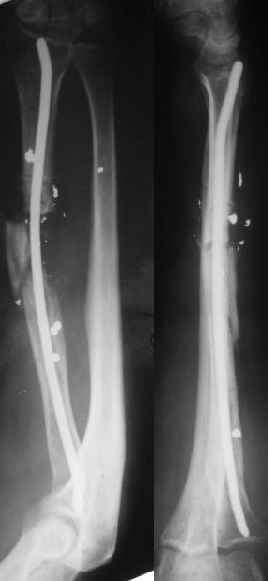

В приложении - снимок по окончании дистракции, и после смены аппарата на стержень (довольно толстый, 5 мм). С входом в канал на центральном отломке пришлось малость попотеть, промежуточный отломок его прикрывал. Но все-таки удалось закрыто проколупать. Надеюсь, дня через 3-4 после операции можно будет передать пациента нейрохирургам. Буду признателен за критику и комментарии.